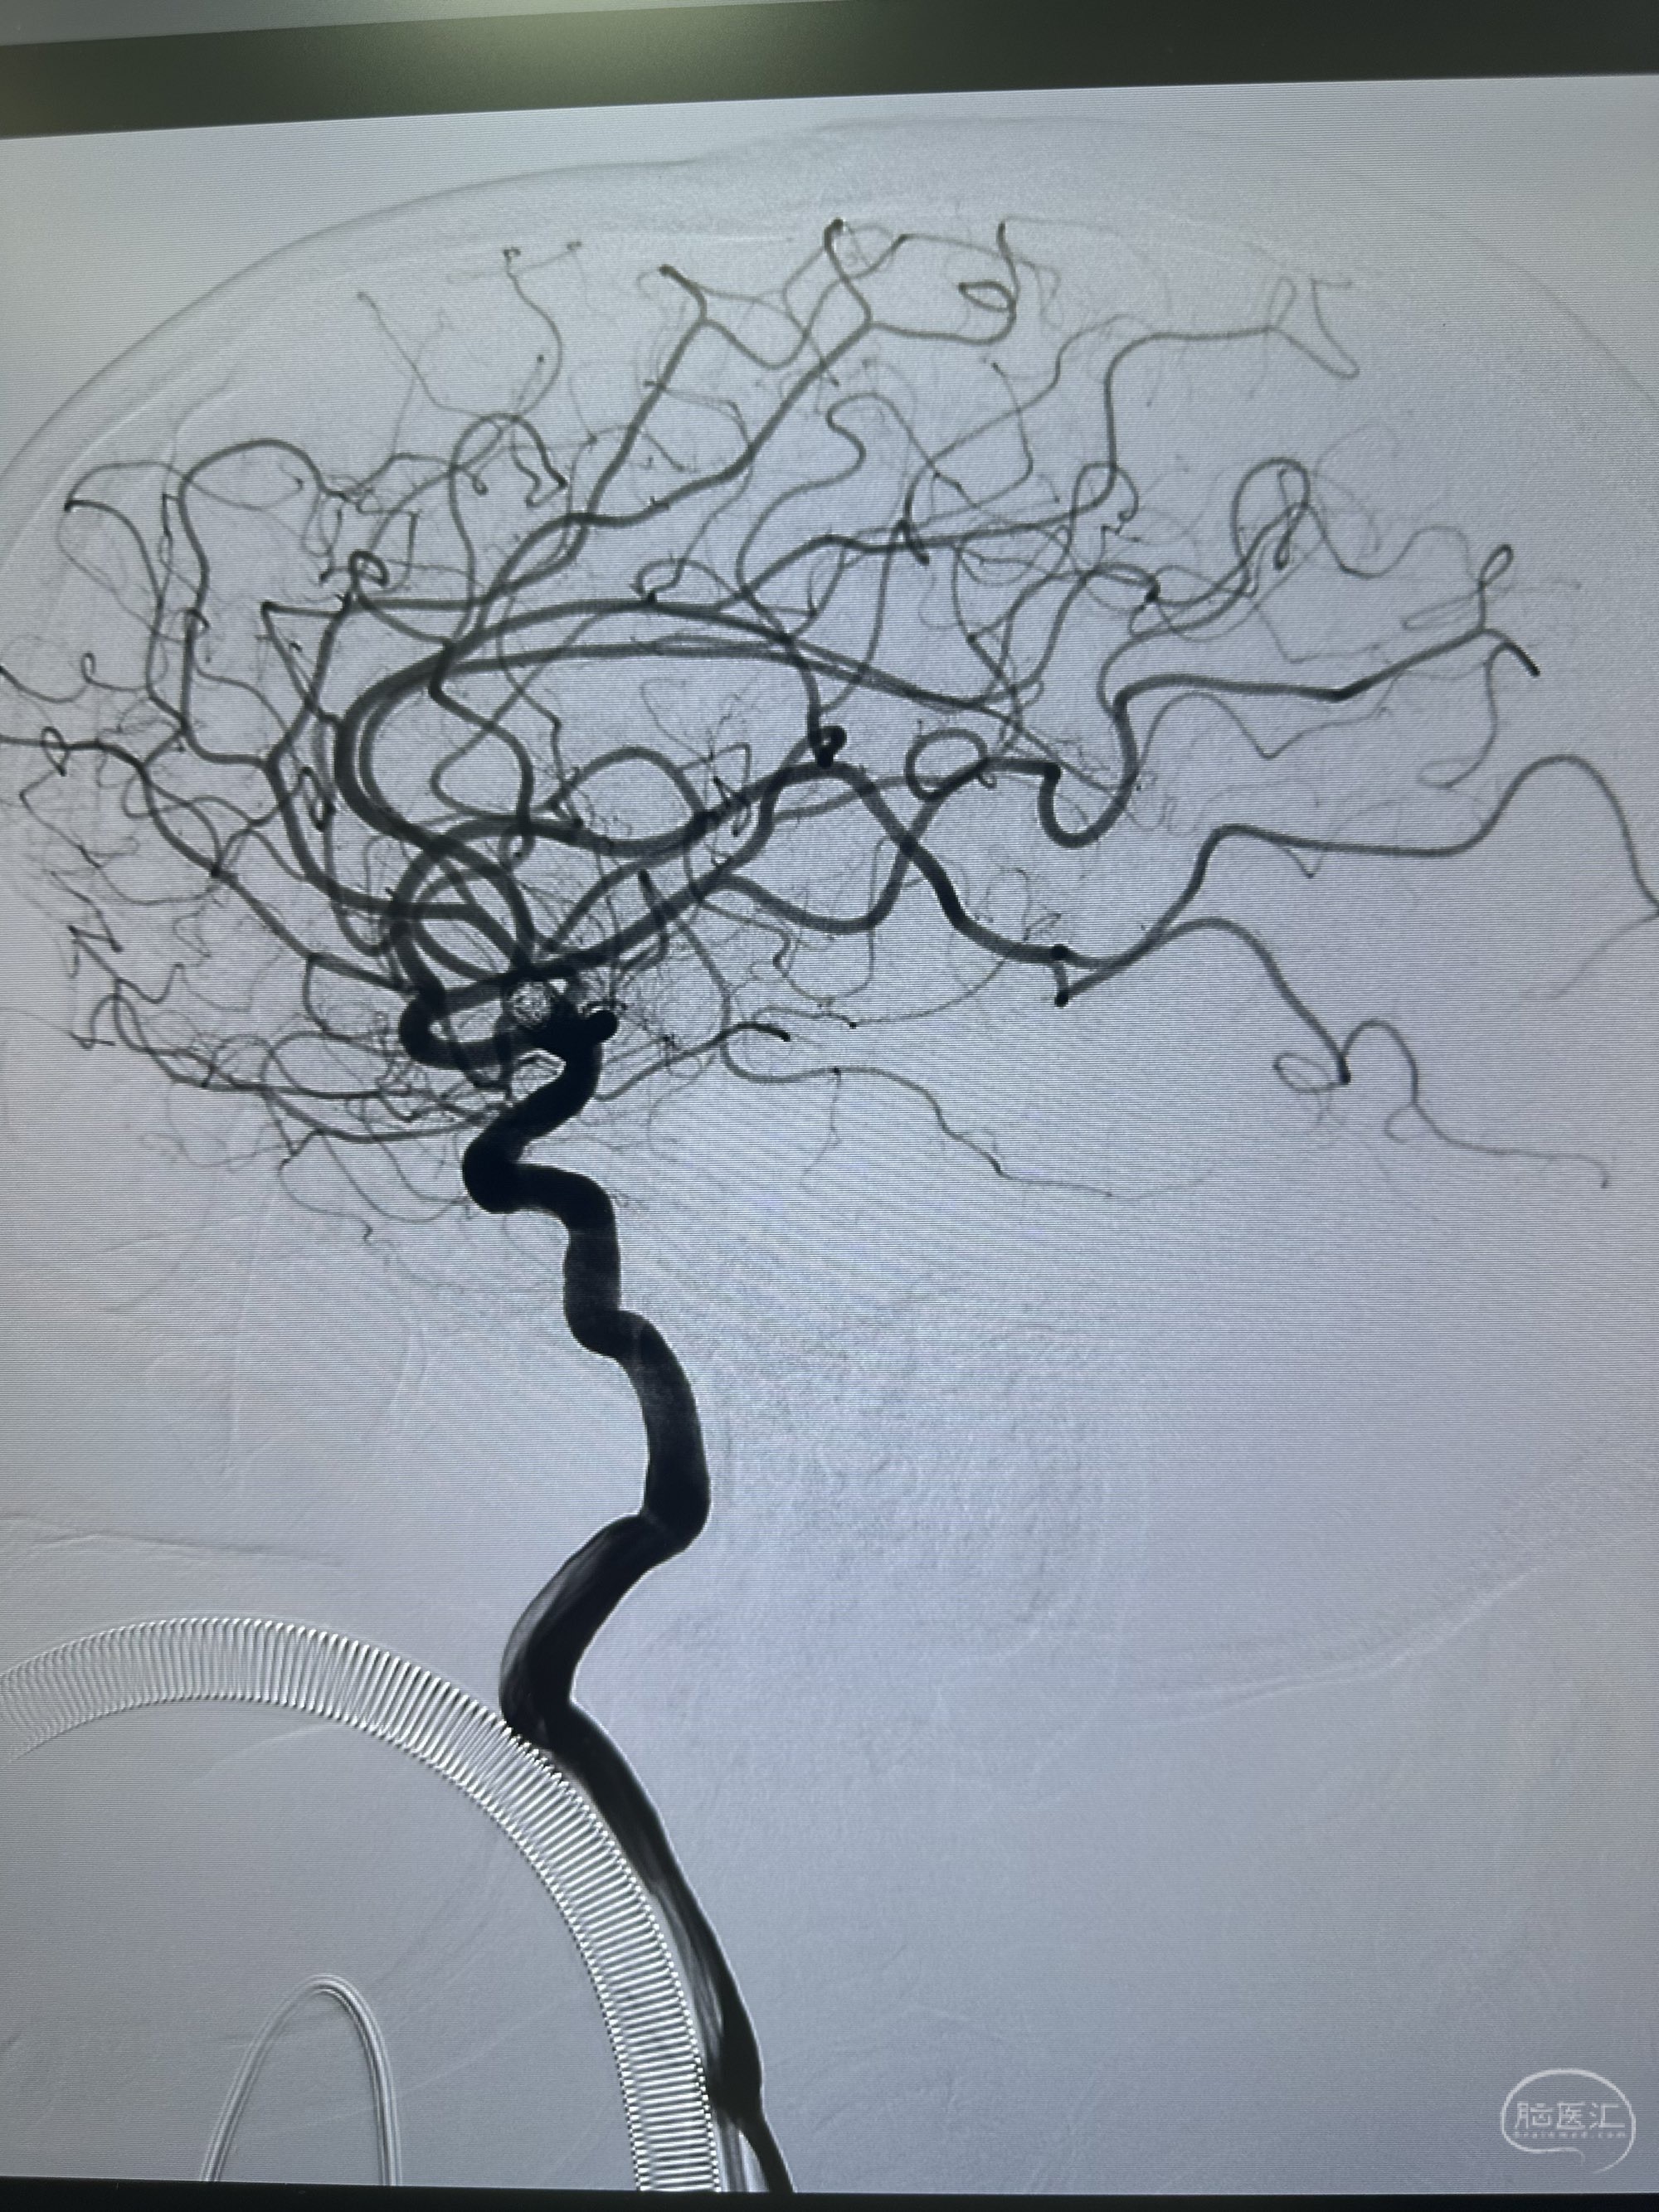

后续填塞三枚ES 3*8,1.5*3,1*3.

最后圈的形态